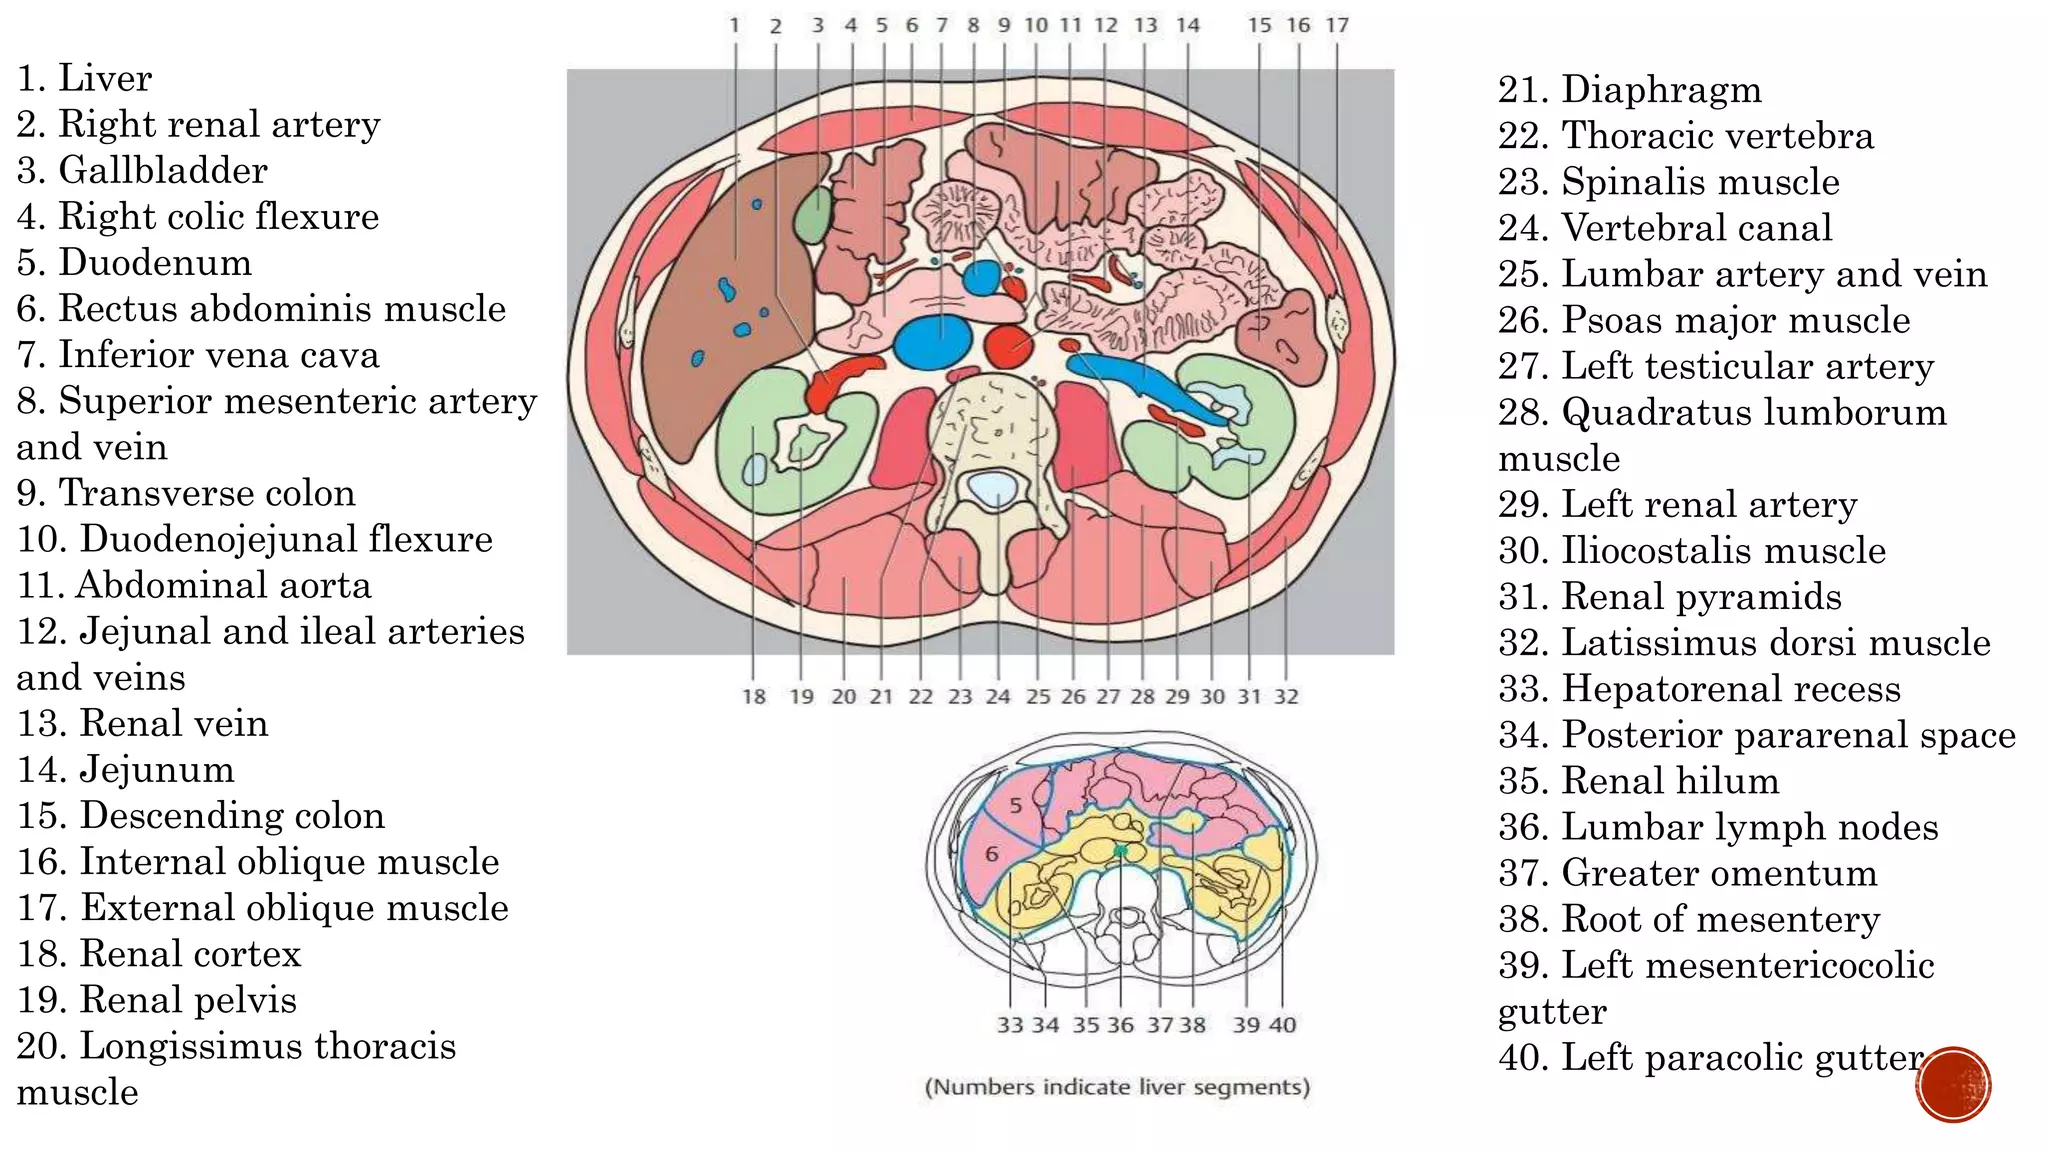

The document describes the anatomy of the abdomen and pelvis region of the human body. It lists over 40 structures and their locations, including major organs like the liver, kidneys, intestines, blood vessels and muscles of the abdominal wall and pelvis. The structures are grouped into sections focusing on different anatomical areas like the abdomen, retroperitoneum, pelvis and gluteal region.